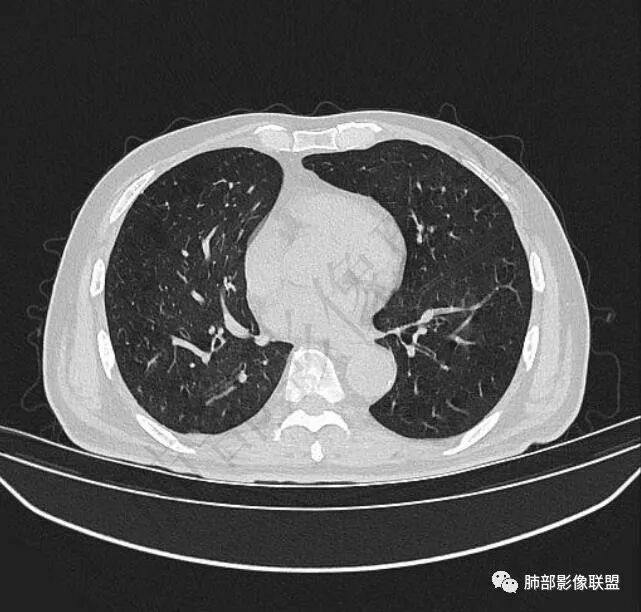

二..发现左肺上叶舌段实性密度小结节影,不规则略呈半环形,边界清楚,未见分叶、毛刺及磨玻璃晕。未见卫星病灶。

9个月后病灶明显增大,边缘较平直,部分膨隆,锁扣样外观,仍旧缺乏典型深分叶及张力,未见胸膜凹陷。

再1个多月后病灶继续增大,较明显不均匀强化,肺门一侧见低密度区。病灶边缘相对不清,可见毛刺。